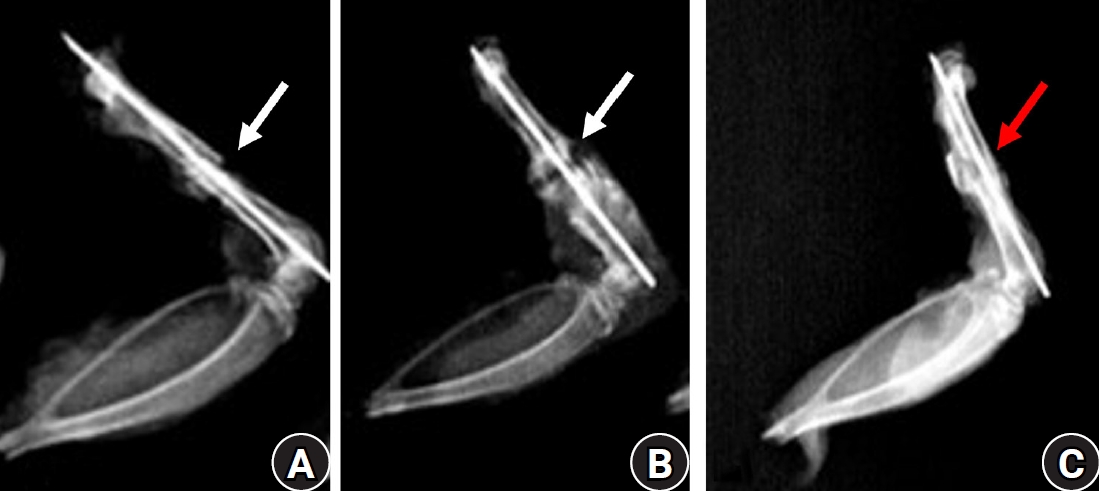

Fig. 5.

Immunohistochemically stained sections showing the expression and intensity of vascular endothelial growth factor (VEGF) and type X collagen in all three groups at 2 weeks after fracture. Notably, expression is higher in the control group, as shown by the brown staining (scale bars, 50 µm; magnification, ×100).

Immunohistochemical expression of collagen X and VEGF

The immunohistochemical stained slides gave the variable expression of collagen X (COLX) and VEGF. The COLX staining was seen around the mature hypertrophied chondrocytes and near the newly formed bone, while VEGF expression was mostly near the newly formed bone, in extracellular matrix and around blood vessels.

The expression of COLX was less in percentage (P=0.01) and intensity (P=0.02) in experimental animals as compared to controls making IRS significantly lower in these animals (P=0.01) in 2nd week (Table 3, Fig. 5). Pairwise comparisons using Dunn’s post hoc test showed significantly lower percentage, intensity, and IRSs in the diclofenac group compared with the celecoxib group (P=0.05, P=0.04, and P=0.04, respectively) and the control group (P=0.003, P=0.009, and P=0.004, respectively). On the 7th week no significant difference was seen in the expression of COLX among animals.

VEGF expression was significantly reduced in experimental animals compared with controls, both in terms of percentage (P=0.005) and intensity (P=0.006), resulting in a significantly lower IRS (P=0.005) at the 2nd week (Table 3, Fig. 5). Pairwise comparisons using Dunn’s post hoc test demonstrated significant differences in percentage, intensity, and IRSs between the diclofenac group and controls (P=0.001, P=0.002, and P=0.001, respectively), as well as between the celecoxib group and controls (P=0.04, P=0.04, and P=0.05, respectively).

Correlation between immunohistochemical expression and healing scores

The COLX and VEGF expression was seen to be in significant positive correlation with total healing score (r=0.76, P=0.002; r=0.66, P=0.01 respectively). While in the 7th week they did not show any significant correlation.

Correlation among immunohistochemical expression

Both VEGF and COLX were in significant positive correlation with each other in the 2nd week (r=0.7, P=0.006) while in the 7th week no correlation was seen.